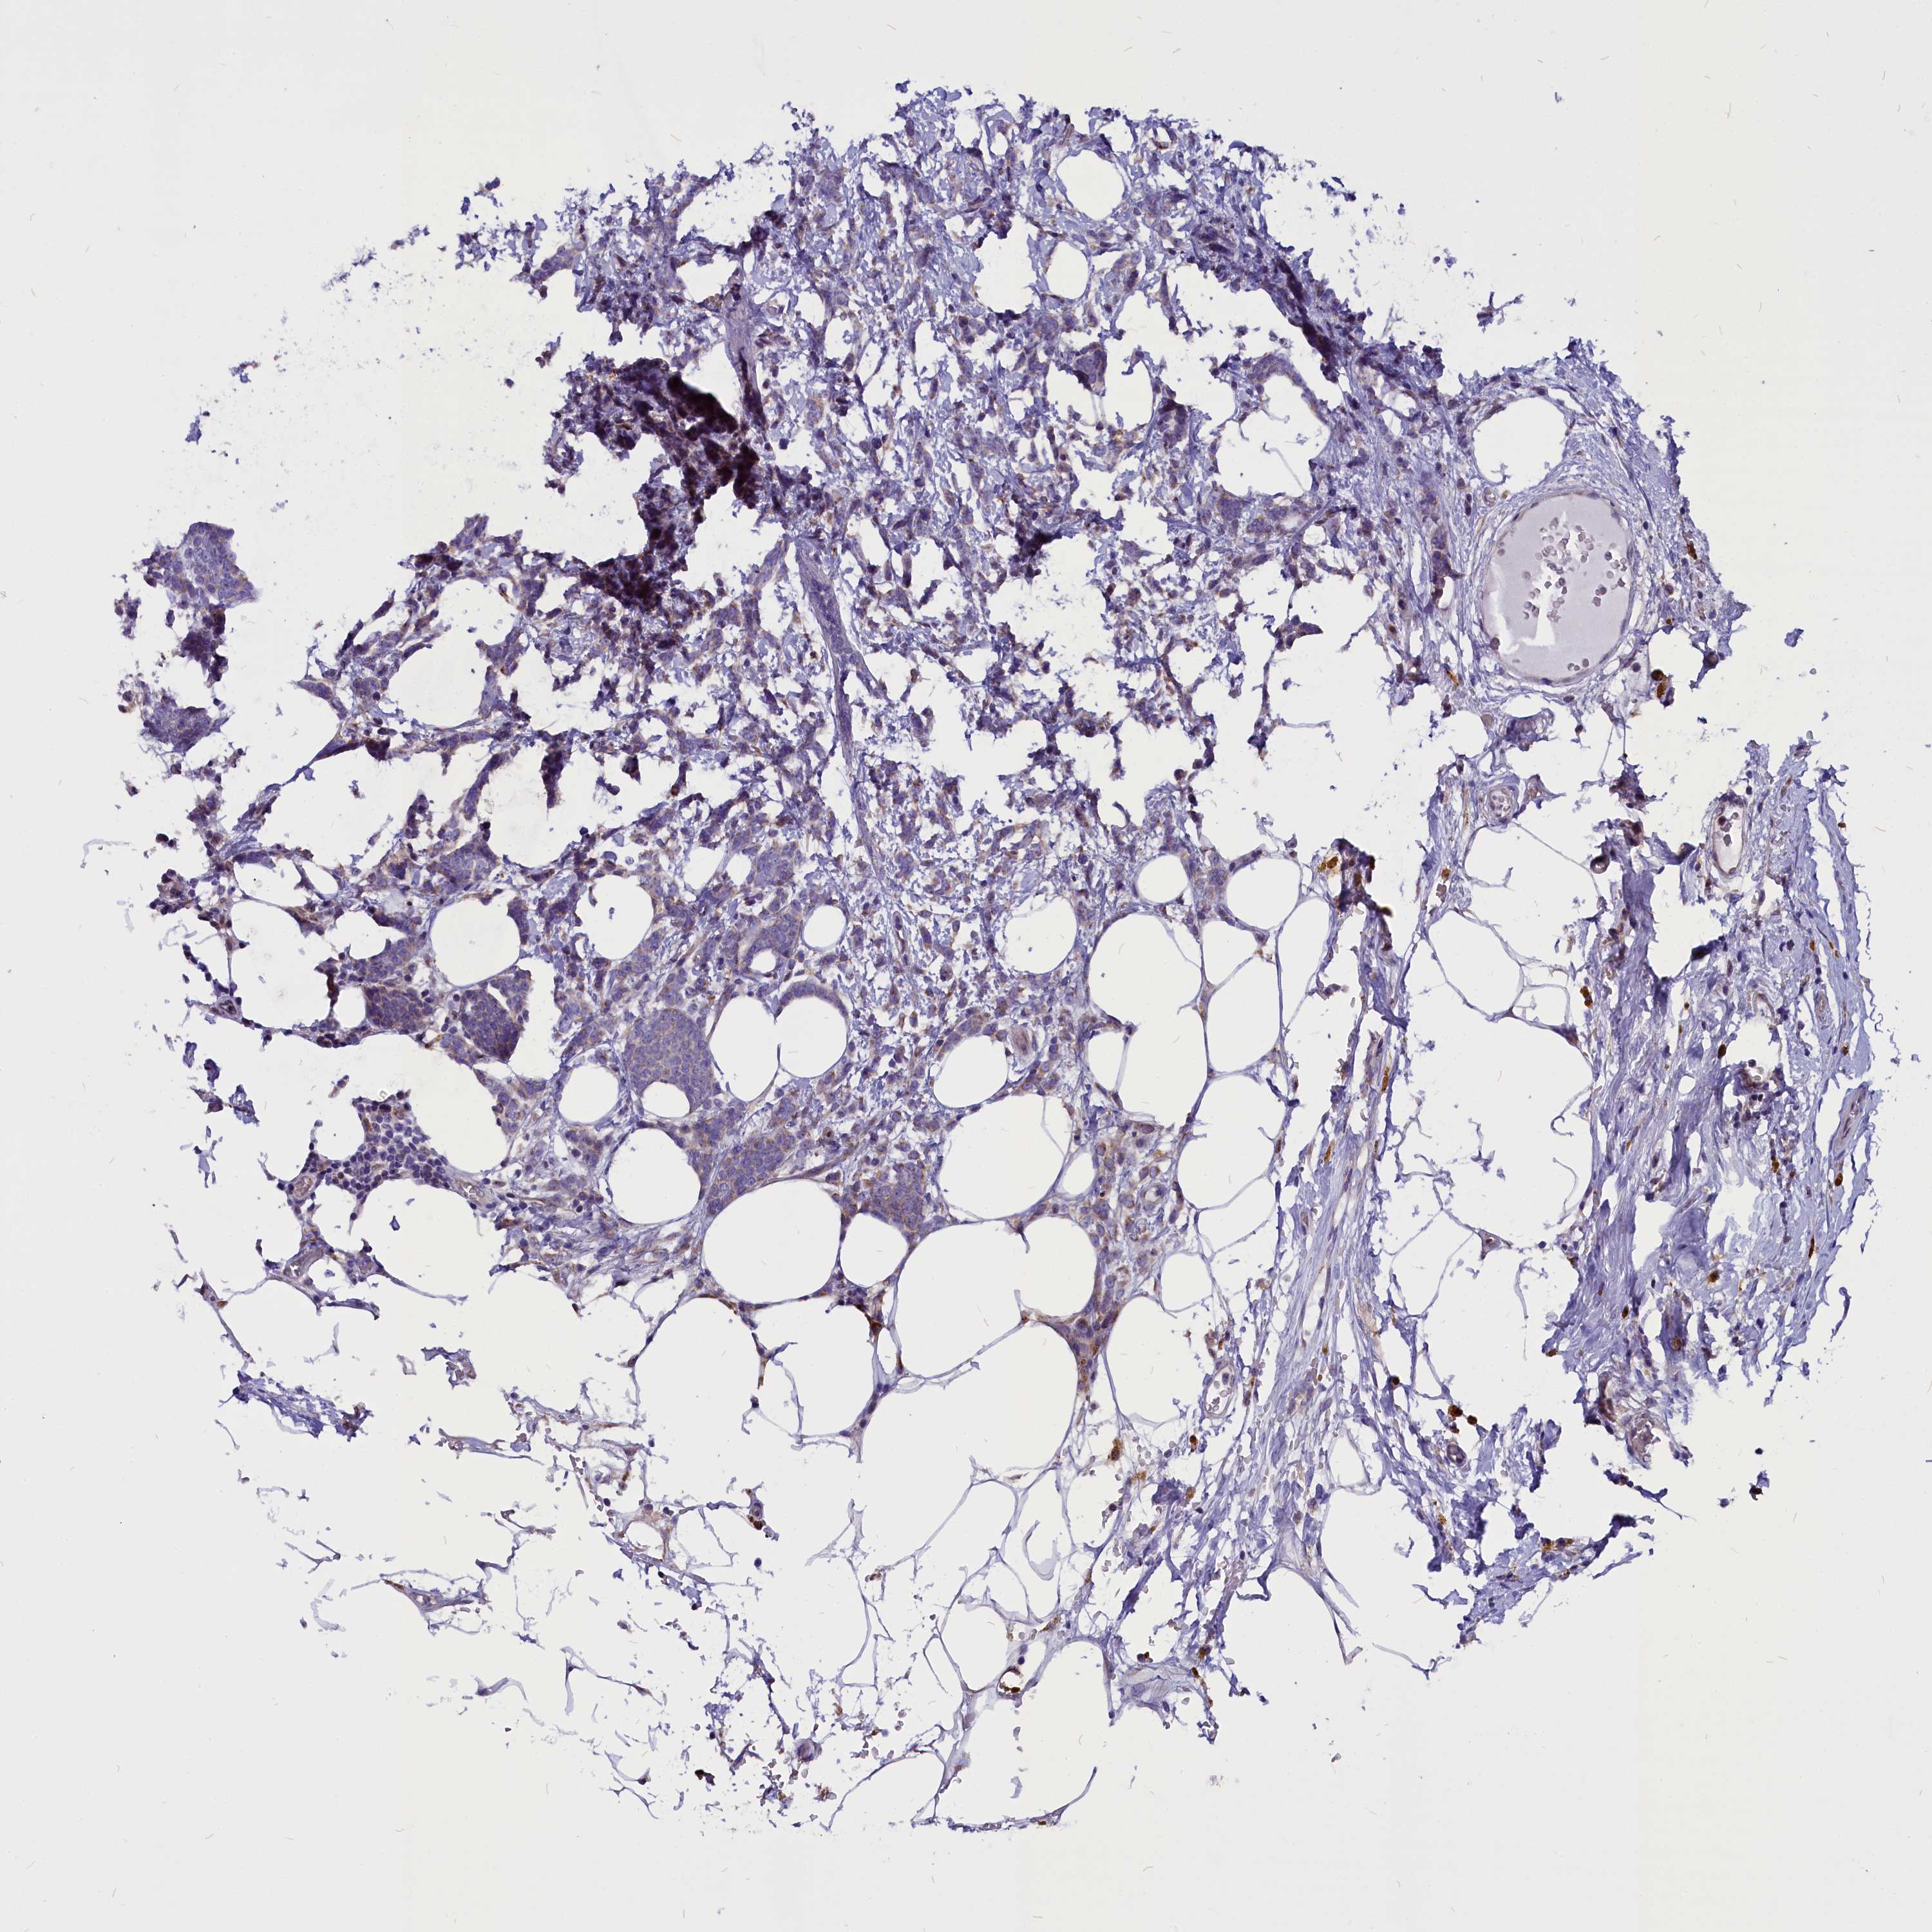

CANCER BREAST CANCER Show tissue menu

BRCA TCGA BRCA VALIDATION PROTEIN EXPRESSION

ANTIBODIES

AND

VALIDATION